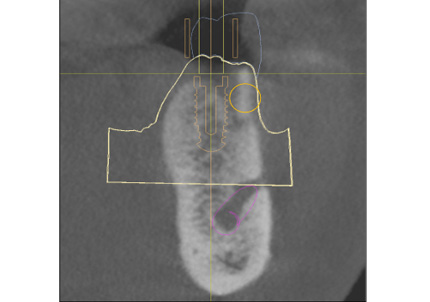

【ソケットシールドテクニックにより保存した歯牙片の内側にインプラントを埋入するCTシミュレーション】

【上記シミュレーションにて作製したガイドを用いたインプラント埋入】

← 右上1番 SST CT画像

※ CT画像にて歯根片が確認できる

← 左上2番 SST CT画像

← 右上2番 通常の埋入 CT画像